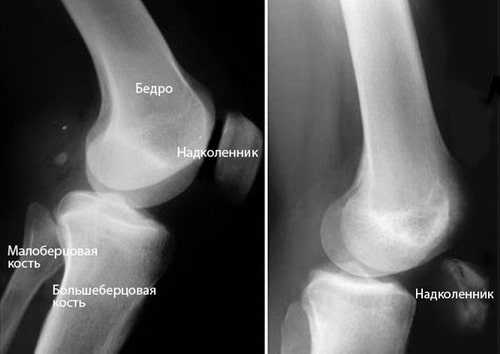

(Слева) При рентгенографии пациента, занимающегося горными лыжами, после падения, в боковой проекции определяется крупное мягкотканное образование в переднем дистальном отделе бедра с дистальным смещением надколенника (низколежащего) и его ротацией. Эти признаки предполагают разрыв четырехглавой мышцы при соответствующей клинической картине.

2. Рентгенография при травме четырехглавой мышцы:

• Низколежащий надколенник (низкий надколенник) с разрывом сухожилия тяжелой степени

• Отрывной фрагмент верхней части надколенника

• Отек мягких тканей над надколенником

• Часто определяется выпот в коленном суставе

• Кальцификаты в сухожилиях четырехглавой мышцы

Рентгенографическое исследование проводится прямо и с боку. При разрыве наблюдаются 4 признака:

- коленная чашечка смещается вниз;

- увеличивается масса ткани над чашечкой;

- сужается тень травмированного сухожилия, воспаление уже очевидно;

- наблюдаются отложения кальция.

Рентгенография. Диагностика по методике рентгенографии позволяет визуализировать не только полное разделение сухожилия, но и патологическое смещение коленной чашечки вниз.

На изображении слева (в боковой проекции) можно увидеть нормальное положение коленной чашечки. Изображение справа показывает характерное при разрывах сухожилия смещение надколенника вниз.